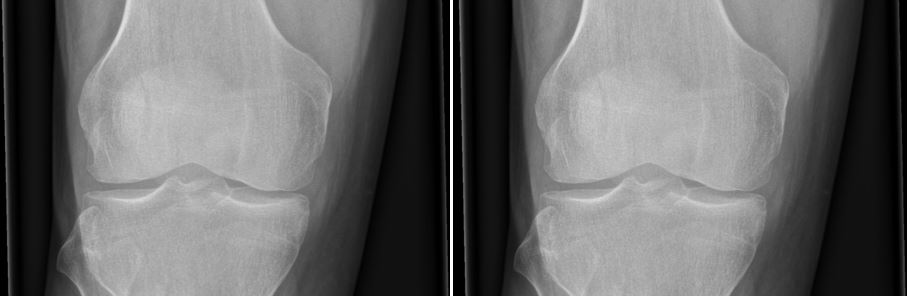

This is a normal knee X-ray as would be expected with PFS

Case courtesy of Dr Andrew Dixon, Radiopaedia.org. From the case rID: 36689